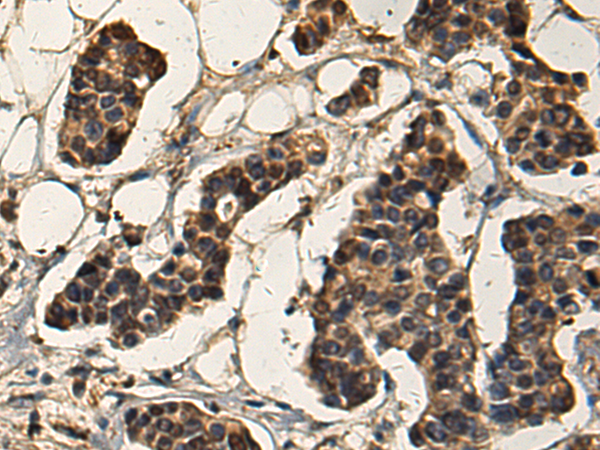

分类: 科研抗体货号: P10438别名: AP2REP; AP-2rep; HSPC122应用: IHC反应种属: Human, Mouse